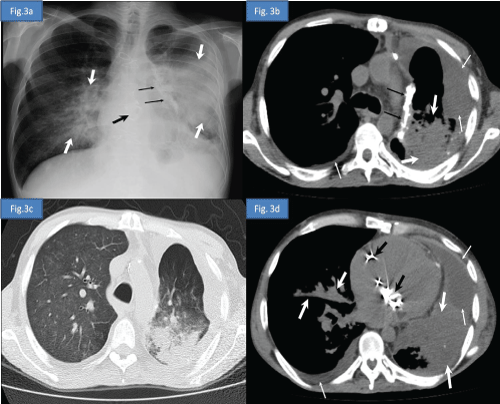

A 39 year-old male patient was diagnosed as thymoma in 1997 and myasthenia gravis (MG) in 2000 respectively. He was administered radiotherapy in 1997, chemotherapy in 2004 and undergone thymectomy in 2011 for the treatment of thymoma. He received deflazacort and pyridostigmin for the treatment of MG between 2000 and 2012. One year after the thymectomy he applied to emergency service with the complaints of dispnea, loss of appetite and bilateral lower extremity edema. He was hospitalized due to congestive heart failure and pneumonia. Postero-anterior chest radiography and high-resolution computed tomography (HRCT) of the thorax were reported as opportunistic infection (Figure 3a- 3d) Sputum cultures yielded acinetobacter baumanii and cytomegalovirus. He was consultated by immunology and allergy service due to febrile drug-resistant pneumonia. Medical history, clinical findings and laboratory results of the patient were determined to be compatible with the diagnosis of GS.

Figure 3a: Postero-anterior chest radiography demonstrates decreased volume of the left hemithorax, bilateral heterogeneous consolidation areas more prominent in left lung secondary to pneumonic infiltration (white thick arrows), left mediastinal pleural calcified plaque (black thin arrows), prosthetic cardiac valves (black thick arrow) and obliteration of the left costodiaphragmatic sinus due to pleural effusion.

Figure 3b: Axial computed tomography image at the upper thoracic level in soft tissue window and in lung window.

Figure 3c: Axial computed tomography image at the lower thoracic level and in soft tissue window

Figure 3d: Axial computed tomography image show decreased volume of the left lung, bilateral pleural effusion (thin white arrows), prosthetic cardiac valves (black thick arrow), left mediastinal pleural calcified plaque (black thin arrows), bilateral heterogeneous consolidation areas more prominent in left lung and extensive ground-glass opacities in right lung secondary to pneumonic infiltration (white thick arrows). View Figure 3